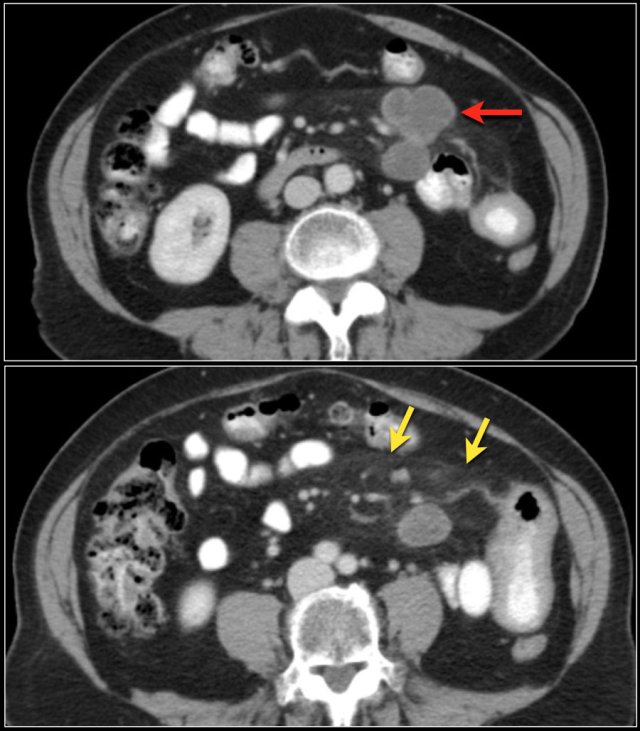

Here another adenocarcinoma located in the jejunum.

There are multiple lymph nodes (red arrow) and there is fat stranding (yellow arrows).

It should not be mistaken for mesenteric panniculitis as these large necrotic lymph nodes are pathologic.